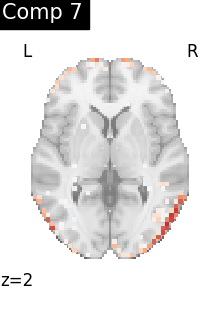

One plot of each component

for i, cur_img in enumerate(iter_img(dictlearning_components_img)):

plot_stat_map(

cur_img,

display_mode="z",

title=f"Comp {int(i)}",

cut_coords=1,

vmax=0.1,

vmin=-0.1,

colorbar=False,

)